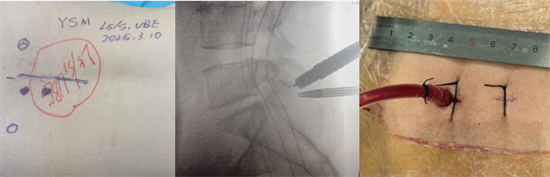

術(shù)中圖片顯示,切口7mm,僅需縫合1針

患者陽(yáng)某某,女,50歲,因反復(fù)腰部疼痛7年加重,并右下肢疼痛麻木半月到衡南縣人民醫(yī)院就診。骨科二區(qū)主任陳軾接診了患者,門診MRI檢查發(fā)現(xiàn)陽(yáng)女士為典型L5/S1巨大椎間盤(pán)脫出并壓迫神經(jīng)根,保守治療無(wú)效,建議手術(shù)治療。苗驚雷教授與縣醫(yī)院骨科二區(qū)專家團(tuán)隊(duì)為陽(yáng)女士量身定制了無(wú)需內(nèi)固定、創(chuàng)傷更小的UBE微創(chuàng)手術(shù)方案。術(shù)中通過(guò)兩個(gè)7mm的切口,精準(zhǔn)摘除脫出髓核,徹底解除神經(jīng)壓迫。術(shù)后次日,陽(yáng)女士下肢癥狀顯著緩解,已可自主下床活動(dòng)。